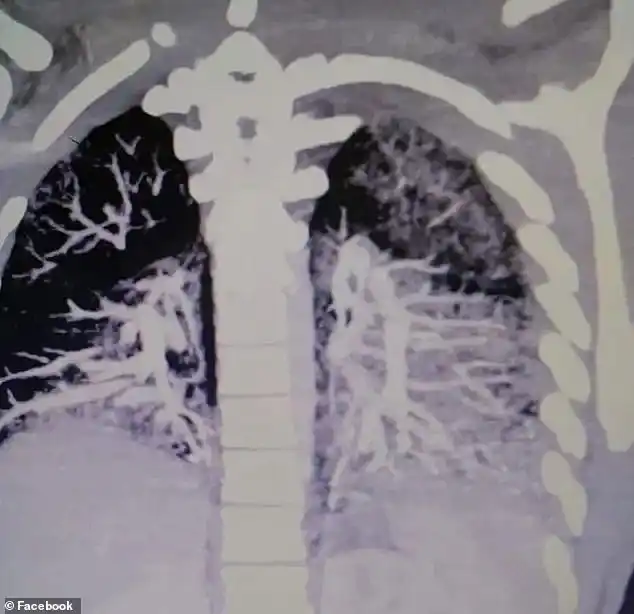

Anthony Mayo, un joven de 19 años de la ciudad de Erie (Pensilvania, EE.UU.), se enfermo de gravedad la semana pasada tras experimentar severos problemas de respiración. Cuando los médicos se percataron de que le diagnosticaron por error bronquitis y una posible neumonía, le hicieron una radiografía y descubrieron así que sus pulmones estaban llenos de aceite solidificado.

Anthony, quien llevaba fumando cigarrillos electrónicos dos o tres veces al día a lo largo de los últimos dos años aproximadamente, tiene ahora los pulmones de un anciano de 60 años fumador de dos cajetillas diarias, describió su padre, Keith Mayo, en una entrevista para Metro US. El joven solía usar aceites con sabores para vapear y estos le jugaron una mala pasada solidificándose en el interior de su organismo.

Stop the vaping and e-cigarettes now! 19 year old Pennsylvania man releases scan of his lungs filled with solidified vape oil. He’d been vaping for two years. Recovering in hospital now while doctors work to clear his lungs. pic.twitter.com/e0NHt9Dfg7

El lunes 16 de septiembre, el joven volvió a la sala de urgencias y las pruebas mostraron que su nivel de oxígeno era del 36 %, muy por debajo del 90% considerado como el mínimo aceptable, por debajo del cual se producen hipoxemia y peligrosos riesgos para la salud. Los médicos le pusieron oxígeno a una saturación del 100% para que pudiera respirar y ayudar a su organismo a expulsar parte del aceite.

Ahora Anthony está siendo sometido a un tratamiento que consiste en calentar una mezcla de oxígeno e hidratarla un poco para que licue el aceite solidificado en sus pulmones y provoque la tos.